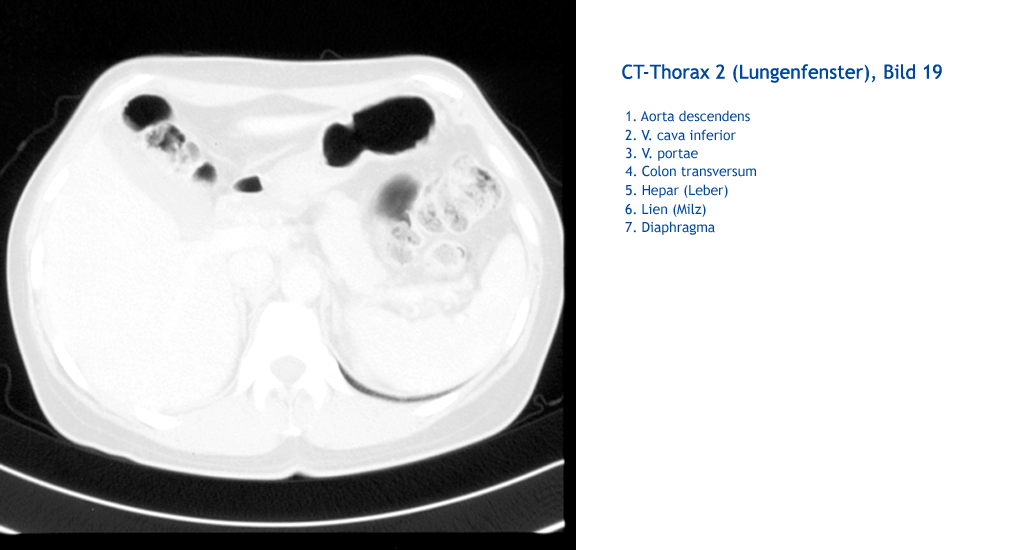

Diaphragma Lien (Milz) Hepar (Leber) Colon transversum V. portae V. cava inferior Aorta descendens